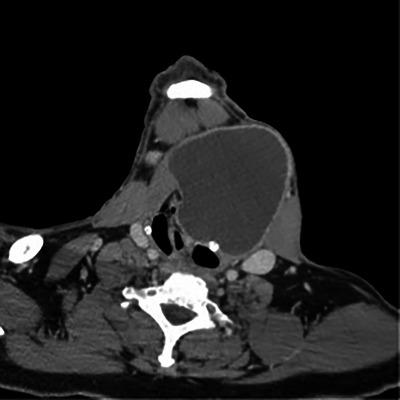

Adult male with dysphagia.